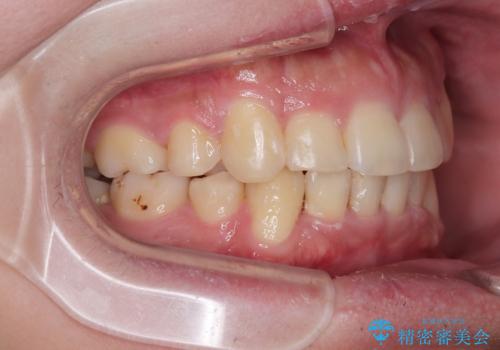

- 八重歯を気にして来院された患者様です。

上下左右の犬歯が八重歯になっており、口元にもやや突出感があるため、上下左右の小臼歯4本を抜歯し、ワイヤー装置にて矯正治療を行うこととしました。